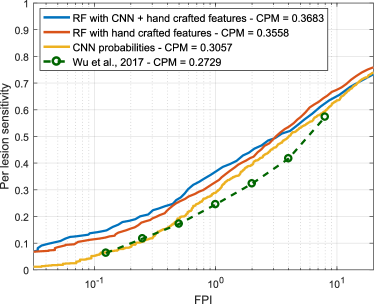

Free-response ROC (FROC) curves were used to evaluate the performance of our red lesion detection method on a per lesion basis. These plots, which are extensively used in the literature to estimate the overall performance on this task, represent the per lesion sensitivity against the average number of false positive detections per image (FPI) obtained on the data set for different thresholds applied to the candidate probabilities. Thus, FROC curves provide a graphical representation of how the model is able to deal with the detection of true lesions in all the images of the data set. We also computed the Competition Metric (CPM) as proposed in the Retinopathy Online Challenge (Niemeijer et al., 2010), which is the average per lesion sensitivity at the reference FPI values . The protocol used by Seoud et al. (2016) was followed when evaluating in DIARETDB1, as indicated in Section 3.1.

Experiment 2 was carried out on e-ophtha to estimate the ability of our method to segment MAs and smaller HEs simultaneously. In this case, a combination of both the DIARETDB1 (MA labels with a level of agreement ) and ROC training sets was used for learning, as we observed that few MAs (only 182 for the entire DIARETDB1 set) are retrieved at agreement. To the best of our knowledge, the only method evaluated on e-ophtha is by Wu et al. (2017), although their analysis is performed on a subsample of 74 images with lesions instead of the full data set. By contrast, we used a more challenging evaluation comprising the entire e-ophtha set, including also the 233 images with no visible sign of DR. Figure 9 presents the FROC curves obtained using each approach. As in the previous experiment, the Wilcoxon signed rank tests showed a statistical significant improvement in the per lesion sensitivity values using the hybrid vector of both deep learned features and domain knowledge with respect to the CNN probabilities and the hand crafted features ( and , respectively).

Table 5 summarizes the CPM values obtained for each experiment and each feature combination, and also using each of the two recently published state-of-the-art methods. Per lesion sensitivities at FPI, which is considered a clinically relevant number of false positives (Niemeijer et al., 2010) are also provided.

When analyzing each individual characterization approach, it is possible to see in Experiment 1 that both the RF trained with hand crafted features and the CNN achieved higher per lesion sensitivities than the method by Seoud et al. (2016) ( and , respectively). This is likely due to the fact that our method for extracting candidates differs from the one used by the alternative approach. Moreover, Seoud et al. (2016) eliminate the lesion candidates occurring within an estimated area around the optic disc center, which is determined using an automated approach. As a consequence, if the diameter of the optic disc is accidentally overestimated by such a method, candidates within valid regions will be suppressed and it will not be possible to recover them afterwards during the classification stage. As seen in Figures 14 and 15, our combined approach is able to discriminate the candidates within the optic disc area and the vascular structures. Hence, instead of using a rigid elimination step based on optic disc segmentation, we let the classifier to decide whether a candidate is actually a true positive or a false positive occurring on an anatomical region. This approach increases the maximum achievable per lesion sensitivity on each image, allowing to train our classifier with a larger amount of false positive lesions and to get a higher sensitivity in test time. A similar observation can be made from the results of Experiment 2, in which the hand crafted features and the deep learning based approach reported higher per lesion sensitivities than those reported by Wu et al. (2017). It must be underlined, also, that the Wu et al. (2017) method was trained on the first half of the images with pathologies on e-ophtha and evaluated on the second half, rather than trained on a separate data set and evaluated on the complete set, as in our case. Moreover, it is worth noting that the images of the healthy patients were also included during evaluation to get a more accurate estimation of its actual performance on a real, clinical scenario.

On a per image basis, it is possible to see that the individual approaches trained in Experiment 1 are not able to achieve AUC values higher than those reported by Seoud et al. (2016) (Table 6). This is likely due to the fact that, as indicated by the authors, their method is more accurate for detecting blot HEs and MAs than HEs with other shapes. The images in MESSIDOR were originally graded as R0 and R1 taking into account the number of MAs (Table 3) (Decencière et al., 2014). Hence, being more accurate in the detection of MAs will result in a better ability to distinguish much earlier stages. When individually using the hand crafted features or the CNN, both methods are less precise for detecting MAs but better for discriminating other HEs. This argument is supported by results presented in Figure 8, in which it is possible to see that the per lesion sensitivity values obtained for MA detection are lower than those reported for HEs. Moreover, it was observed that the CNN performed equally or better than the RF trained with manually engineered features on the low FPI regime for MA detection. This explains the behavior observed in Figure 11, where the CNN probabilities achieved a higher AUC value for DR screening and need for referral detection. Nevertheless, the combination of both approaches with the RF classifier consistently improved their individual performance, achieving a much better characterization of the MAs (as observed in the improvements reported in Figure 8(a)) and, consequently, a better discrimination of the DR patients.